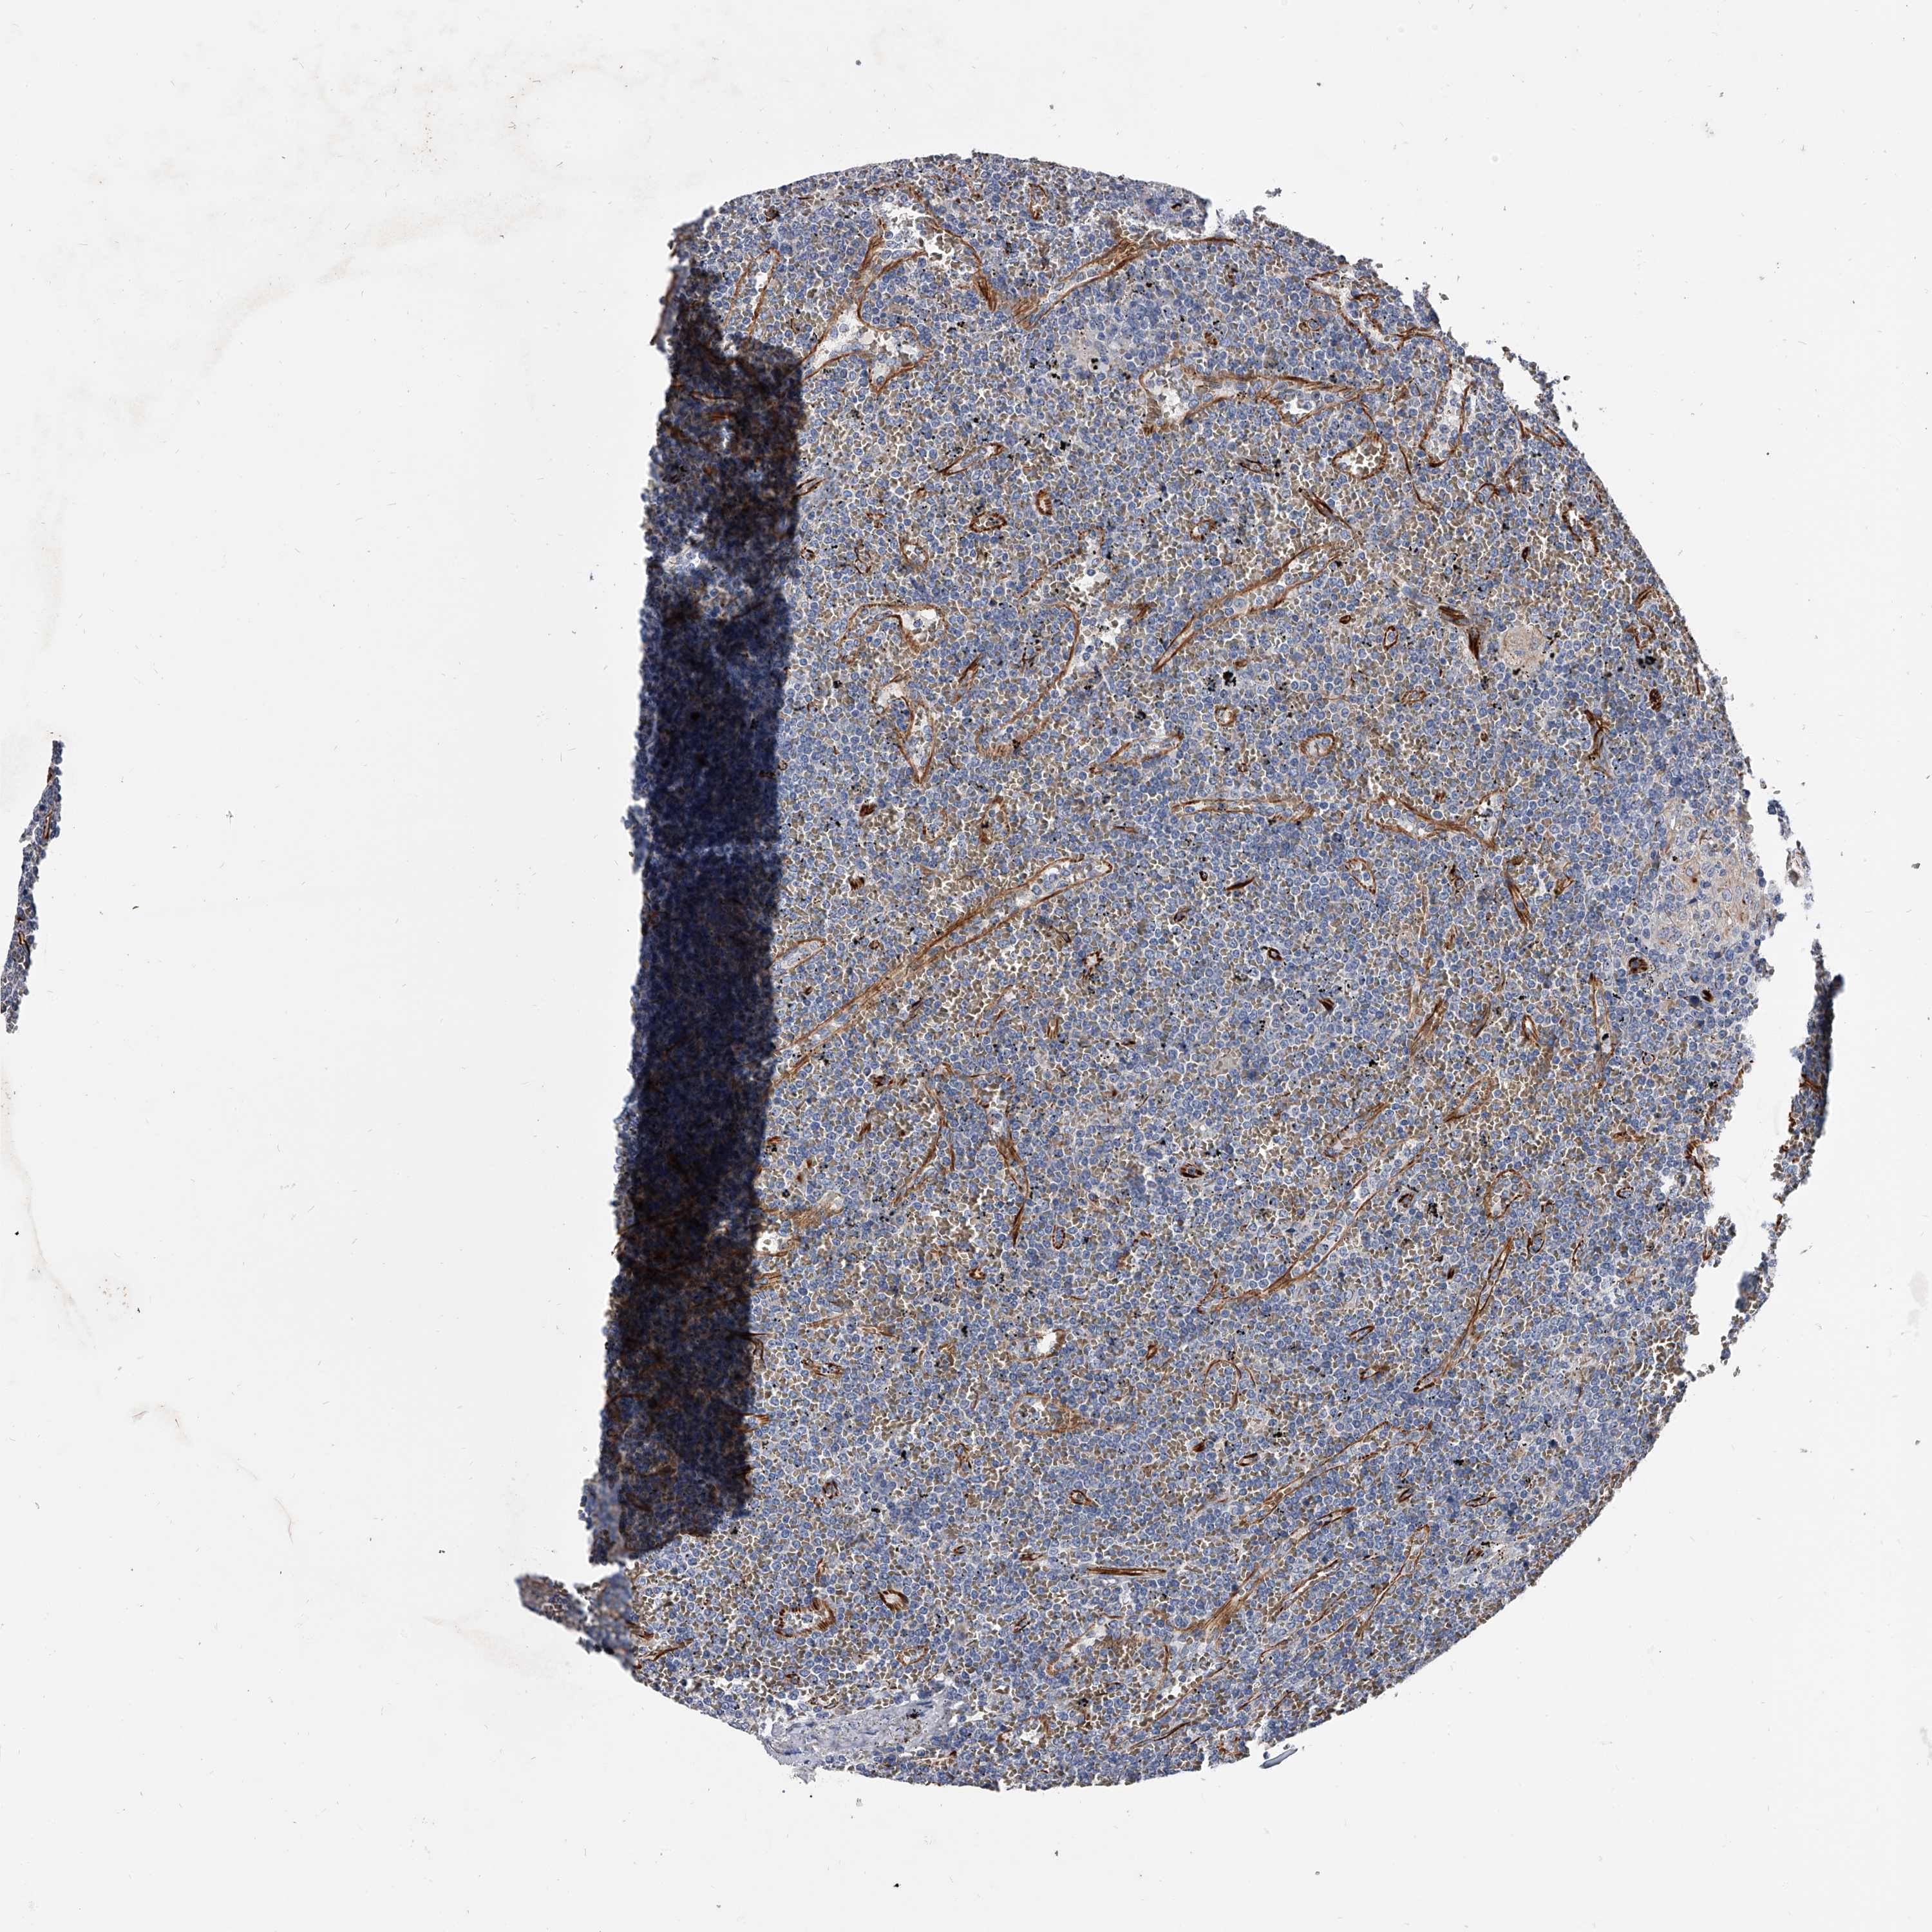

LYMPHOMA